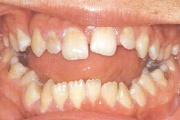

Ruumipuudus eesmiste hammaste osas